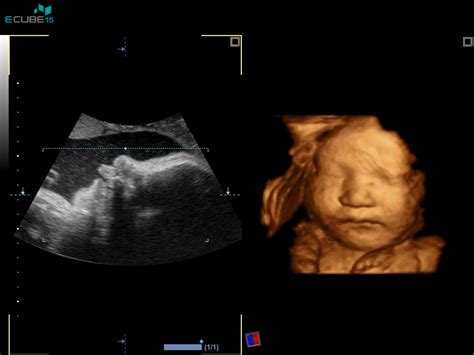

Poleg standardnega 2D ultrazvoka, ki prikazuje dvodimenzionalno, črno-belo sliko, sodobna tehnologija ponuja še naprednejše možnosti. 3D ultrazvok omogoča računalniško rekonstrukcijo tridimenzionalne slike ploda, ki je fotografsko realistična in omogoča staršem vpogled v otrokov obrazek in telo v maternici. Z dodatnim spreminjanjem kota osvetlitve in pogleda na plod lahko sliko še dodatno obogatimo.

Še korak dlje gre 4D ultrazvok, ki dodaja časovno komponento k 3D sliki. To pomeni, da lahko v realnem času opazujemo gibanje ploda - kako se premika, zeha, sesa palec ali se igra. Ta izkušnja je izjemno čustvena za starše in jim omogoča še bolj pristen stik z nerojenim otrokom. Celotna 3D/4D ultrazvočna preiskava se običajno dokumentira s posnetki ali video zapisi, ki jih nosečnica prejme na USB ključku ali CD-ju, kar predstavlja dragocen spomin na nosečnost.

Te napredne ultrazvočne tehnike niso namenjene le ustvarjanju spominov, temveč lahko služijo tudi kot dopolnilo k rutinskim pregledom. Omogočajo podrobnejši vpogled v anatomijo ploda, oceno vedenjskih vzorcev v prvem trimesečju in celo napoved porodne teže. Nekateri centri ponujajo tudi specializirane 3D/4D morfološke ocene s podrobnim pregledom plodovega srca in drugih organskih sistemov.